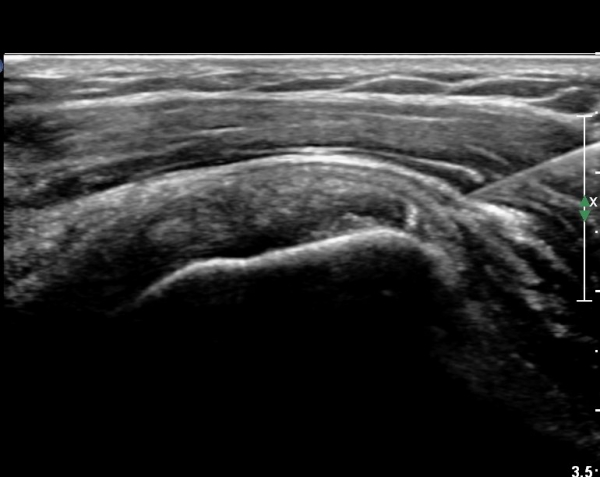

±Ø»ó°Ç Á¾´Ü¸é°Ë»ç¿¡¼­ ±Ø»ó°Ç³» ¼®È¸È­ À½¿µÀÌ °üÂûµÈ´Ù(»çÁø 4).